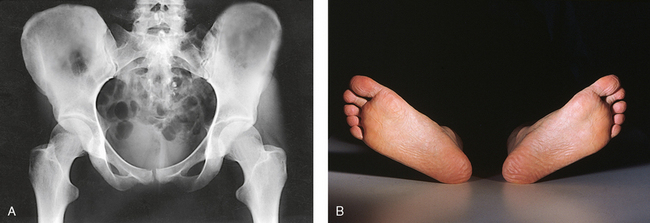

• Unless contraindicated because of trauma or pathologic factors, medially rotate the feet and lower limbs about 15 to 20 degrees to place the femoral necks parallel with the plane of the image receptor (IR) (Figs. 7-15 and 7-16). Medial rotation is easier for the patient to maintain if the knees are supported. The heels should be placed about 8 to 10 inches (20 to 24 cm) apart.

Fig. 7-15 A, AP pelvis with femoral necks and trochanters poorly positioned because of lateral rotation of limbs. B, Feet and lower limbs in natural, laterally rotated tabletop position, causing poor profile of proximal femora in A.

Fig. 7-16 A, AP pelvis with femoral necks and trochanters in correct position. B, Feet and lower limbs medially rotated 15 to 20 degrees, correctly placed with upper femora in correct profile in A.